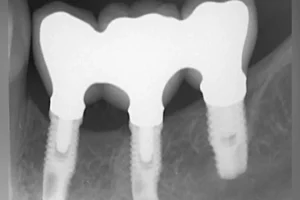

Dental implants are implants that are very compatible with human physiology and are implanted into the alveolar bone, so that the rest of the implants